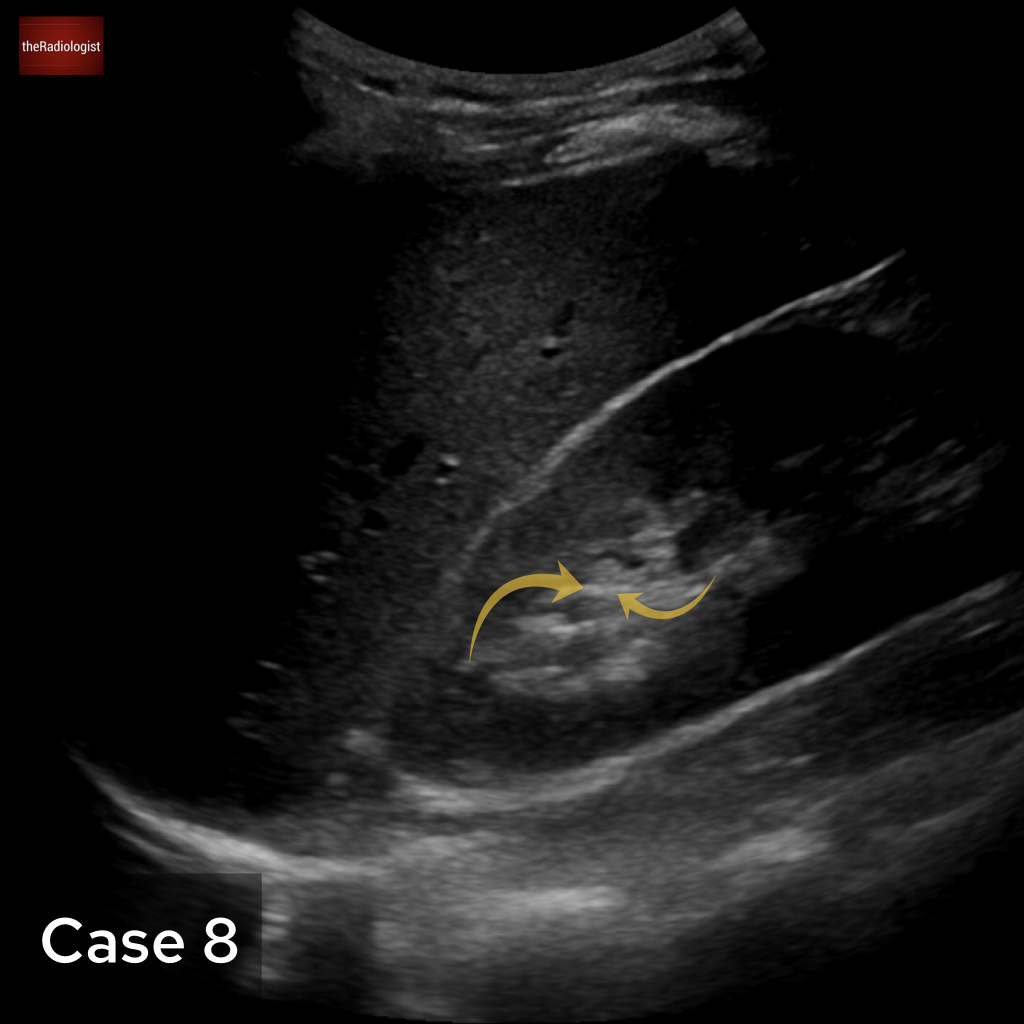

Case 8

Another abdominal ultrasound for case 8. What is the arrow pointing at?

Choose from one of the following options: